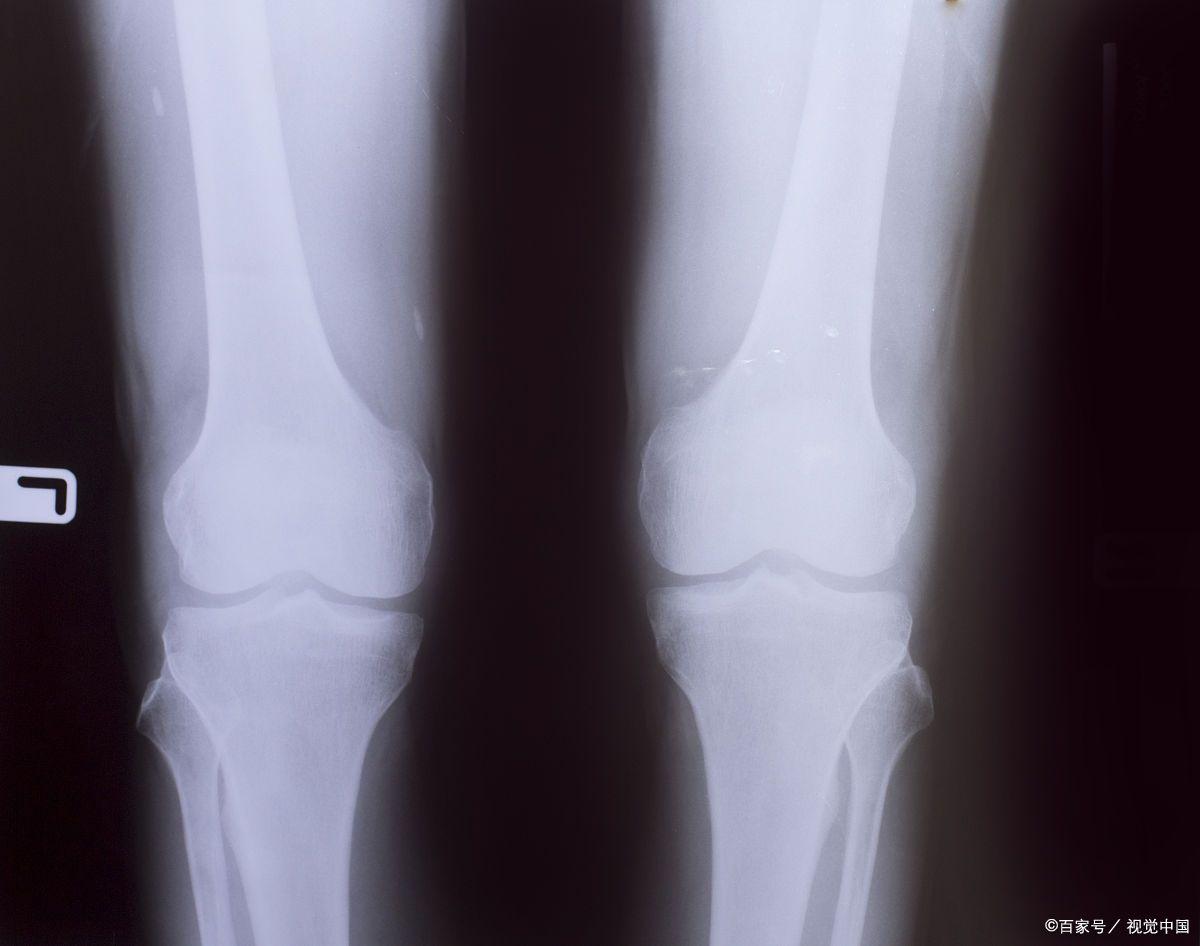

但另一方面,进入青春期发育,儿童骨骺逐渐钙化,进入高结束阶段, 直到骨骺线完全闭合,身高增长结束。

青春后期:性器官和第二性征继续发育成熟,身高增长率放缓,直至骨骺完全融合,生长停止。